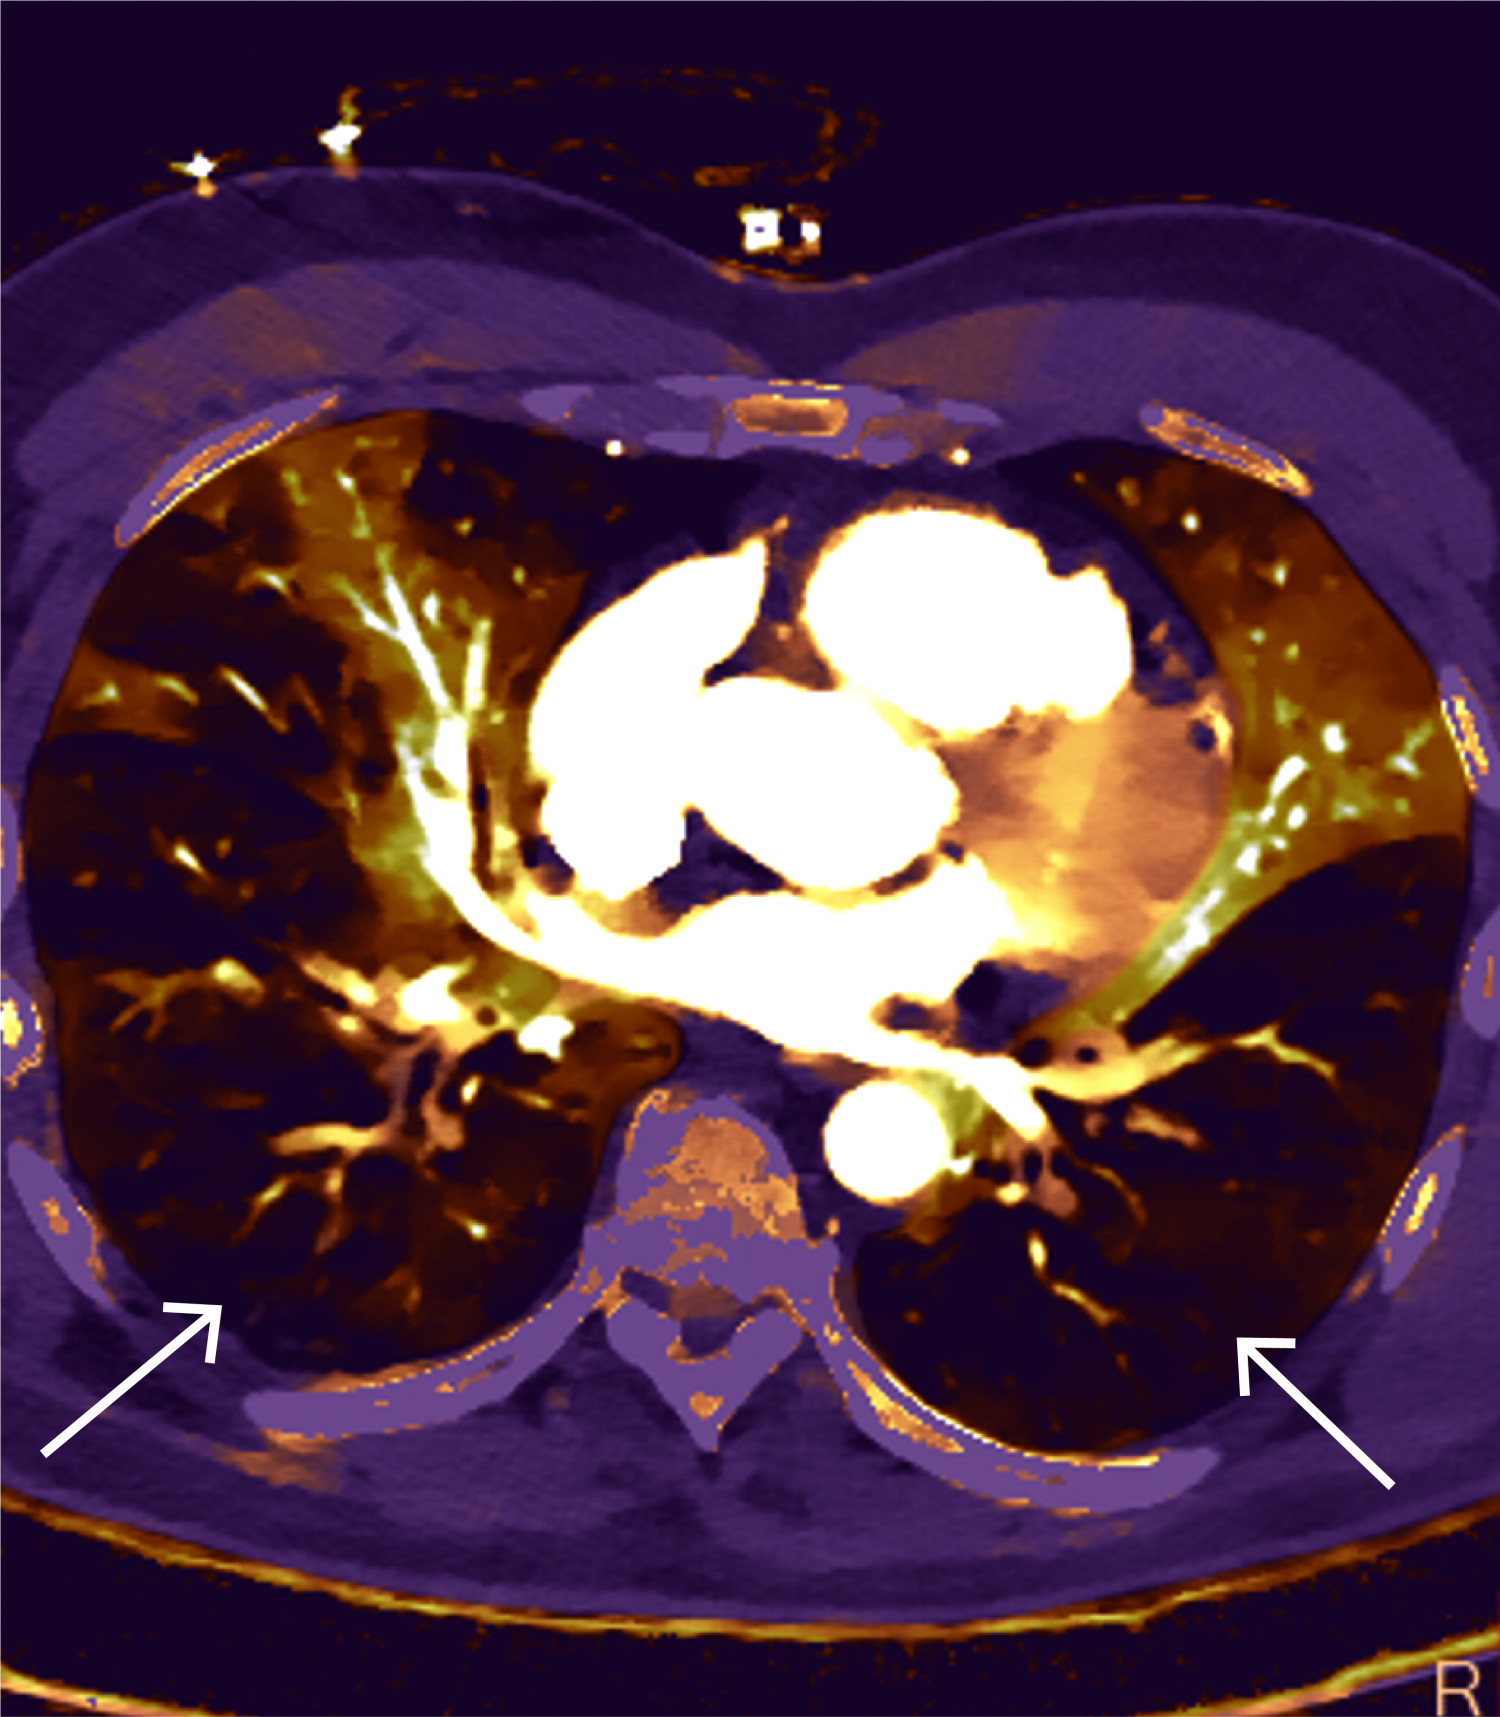

CT toraks med lungeemboliprotokoll viste sadelemboli, med tromber ut i de fleste større lungearterier og med affeksjon av alle lungelapper på lobært og segmentalt nivå (figur 4 og 5). Størst utfall var i underlapper. Aortadisseksjon ble ikke påvist.

Høyre ventrikkel-svikt er en fryktet komplikasjon ved massiv lungeembolisme og ses akutt i varierende alvorlighetsgrad hos 45 % av lungembolipasientene (3). Mekanismene i utviklingen av høyre ventrikkel-svikt i denne situasjonen er sammensatt. Sentrale lungeemboluser som okkluderer store deler av lungekarsengen, fører til at høyre ventrikkel må pumpe mot høy pulmonal vaskulær motstand (økt høyre ventrikkel-afterload). Høyre ventrikkel er tynnvegget og ikke konstruert for å tåle akutt afterloadøkning. Når dette skjer, oppstår redusert høyre ventrikkel-funksjon og kompensatorisk dilatasjon (figur 8). Sekundært til dette overskyves ventrikkelseptum mot venstre ventrikkel og gir redusert diastolisk fylning. Dette medfører redusert hjerteminuttvolum og koronar hypoperfusjon, med sekundær iskemi og ytterligere biventrikulær svikt. Iskemien forsterkes av hypoksemi og det faktum at høyre ventrikkel har økt oksygenbehov. Dilatasjonen av høyre ventrikkel gir samtidig strekk på trikuspidalringen, med sekundær trikuspidalinsuffisiens som også bidrar til redusert venstre ventrikkel-fylning. Det hele kan føre til sirkulatorisk dekompensasjon i form av obstruktivt sjokk, og i verste fall hjertestans (2, 3).